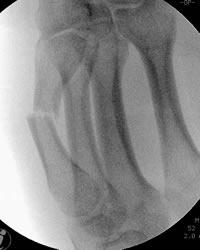

läßt sich leicht mit der retrograden Nagelung verwirklichen. Dabei wird an der Basis des MHK mit dem Pfriem der Markraum eröffnet. Danach weirden ein oder zwei 1.8 mm oder 2 mm starke Kirschnerdrähte eingebracht. Die Drähte werden mit dem stumpfen Ende, das leicht gebogen wird, eingeschoben. Die scharfe Spitze wird abgekniffen und der Draht in ein Jacobsfutter eingespannt. Mit der gebogenen Spitze läßt sich die Fraktur durch Drehen des Drahtes reponieren.

Anterograde Nagelung der Köpfchenfraktur am Mittelhandknochen.